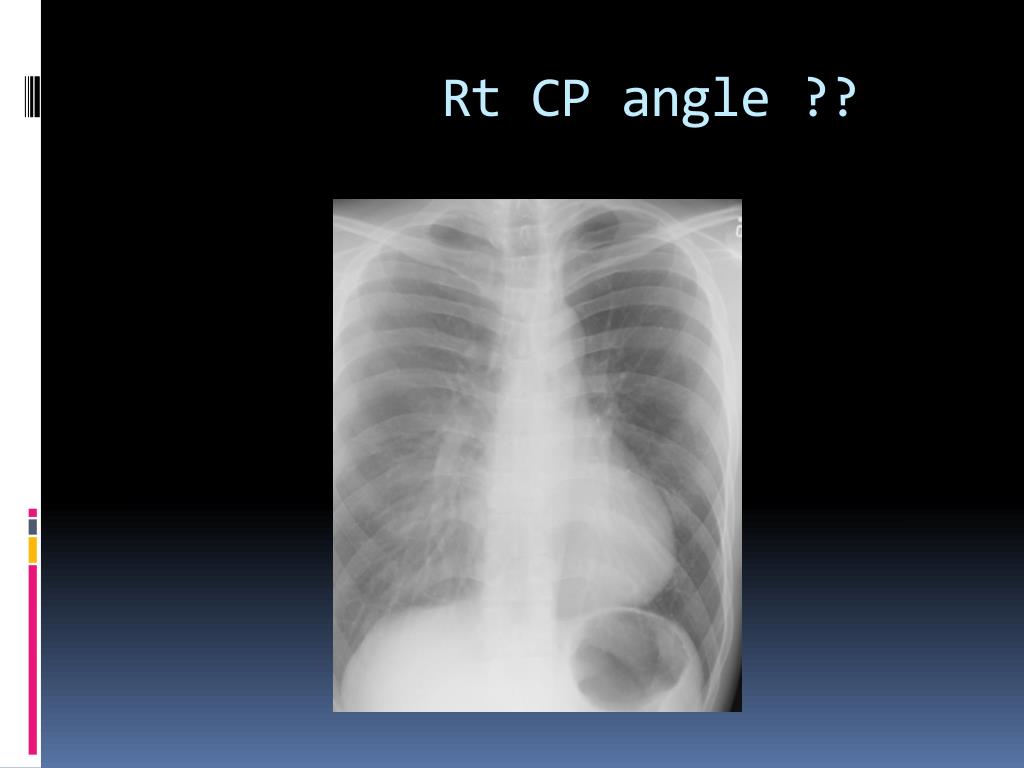

10. Rt CP angle ??